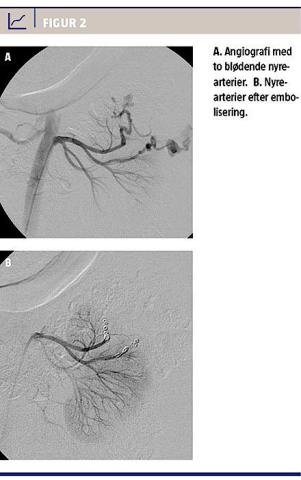

En akut udført CT af abdomen viste en 12 × 10 × 9 cm tumor i venstre nyres øvre pol og stor retroperitoneal blødning. Tumoren blev fundet at være forenelig med diagnosen AML (Figur 1).